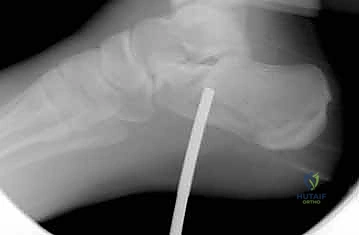

4. التثبيت المؤقت

يتم استخدام أسلاك معدنية دقيقة لتثبيت الشظايا في مكانها مؤقتاً، ثم يتم التحقق من دقة الرد باستخدام جهاز الأشعة السينية داخل غرفة العمليات (C-arm) لضمان عدم وجود أي انزياح ولو بمليمتر واحد.

5. التثبيت النهائي باستخدام الشرائح والمسامير (Plating)

يتم وضع شريحة تيتانيوم (Titanium Plate) مصممة خصيصاً لتطابق الشكل التشريحي لعظم الكعب. يتم تثبيت هذه الشريحة بمسامير قوية لتوفير ثبات ميكانيكي صلب يسمح بالالتئام السليم ويمنع انهيار العظم مرة أخرى. في بعض الحالات التي يوجد فيها فراغ عظمي كبير، قد يستخدم الدكتور هطيف طعوماً عظمية (Bone Grafts) لملء الفراغ.

صور إضافية من داخل غرفة العمليات توضح دقة الإجراء

توضح الصور التالية مدى تعقيد الجراحة والدقة التي يتطلبها تثبيت عظم الكعب، والتي يعكسها التميز الجراحي للأستاذ الدكتور محمد هطيف: